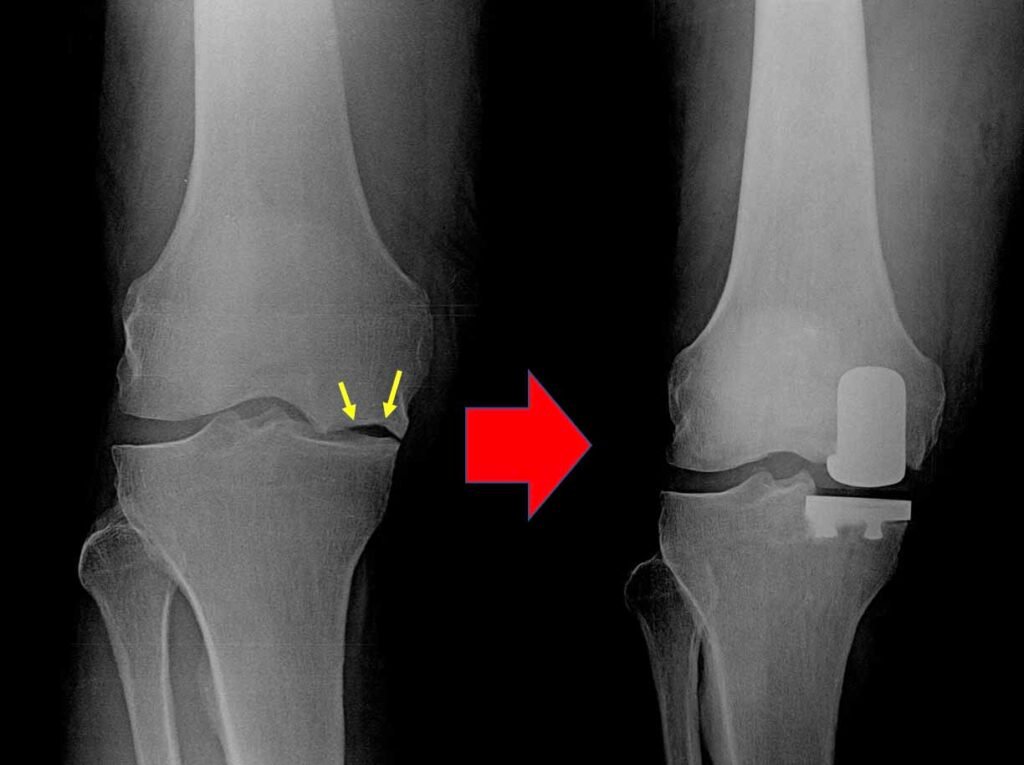

Diagnostic imaging (X-ray/MRI) and blood tests are conducted to ensure precise surgical mapping and safety clearance.

Partial knee replacement treats only one damaged section of the knee, while total knee replacement replaces the entire joint. Partial surgery usually has faster recovery and less pain.